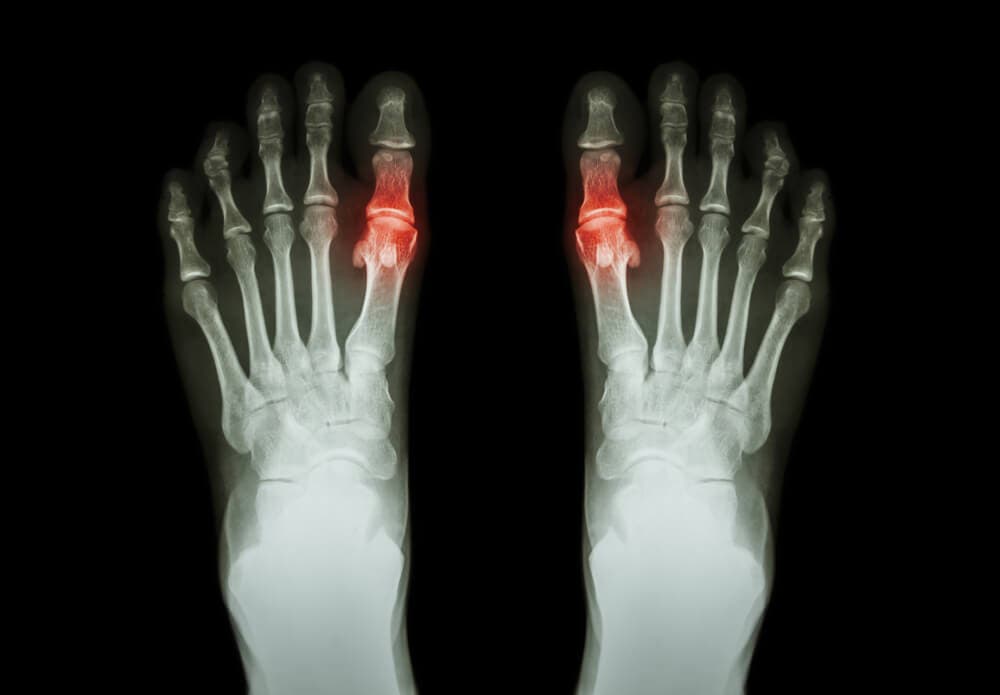

Artrit tenderar att förekomma tillsammans med smärta och svårigheter att röra den drabbade leden eller lederna. Hos vissa innebär det också stelhet och svullnad i samma område. Det kan påverka en led eller flera leder samtidigt. Det kan också vara symmetriskt eller asymmetriskt. Till exempel är reumatoid artrit en symmetrisk typ av artrit som drabbar små leder, såsom fingrarna. Gikt, å andra sidan, är en typ av artrit som tenderar att påverka bara en led.